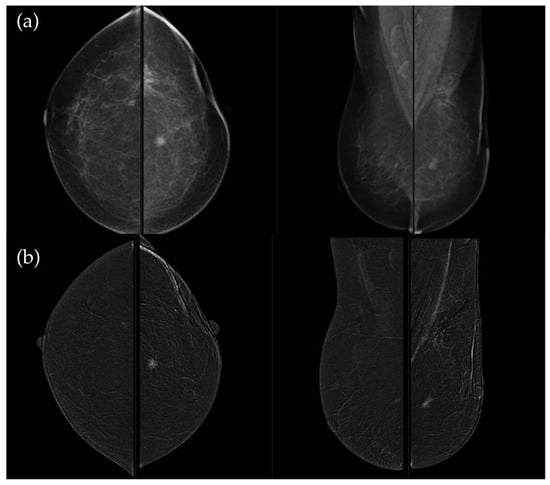

Figure 5. (a) Low-energy CC and MLO views reveal a focal asymmetry with associated suspicious microcalcifications and retraction of Cooper’s ligaments in the upper outer quadrant of the left breast. An oval, well-circumscribed mass with circumscribed margins is seen at the junction of the lower quadrants of the right breast. (b) Recombined contrast-enhanced images (CC and MLO views) demonstrate a large inhomogeneous enhancing area, with two closely situated, partially marginated masses in the upper outer quadrant of the left breast. The right breast lesion shows homogeneous early enhancement without washout on delayed images—findings suggestive of a benign lymph node or fibroadenoma. In the visualized portions of both axillae, no pathologically enhancing lymph nodes are identified. Histopathological analysis confirmed a HER2-enriched breast carcinoma.

Figure 6. (a) Standard CC and MLO images reveal a relatively well-circumscribed, round to oval mass in the left retroareolar region, without suspicious calcifications. The right breast appears unremarkable. (b) On recombined contrast-enhanced images (CC and MLO), the same lesion demonstrates rim enhancement with irregular, heterogeneous internal contrast uptake. The enhancement shows early rapid contrast accumulation—a pattern that raises concern for malignancy. In the visualized portions of both axillae, no pathologically enhancing lymph nodes are identified. Histopathological examination confirmed the diagnosis of triple-negative breast carcinoma.